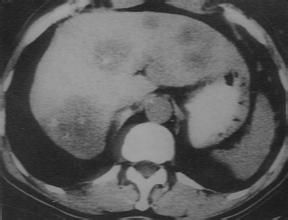

7.CT表現為混合不勻等密度或低密度占位,典型的呈現“牛眼”征;